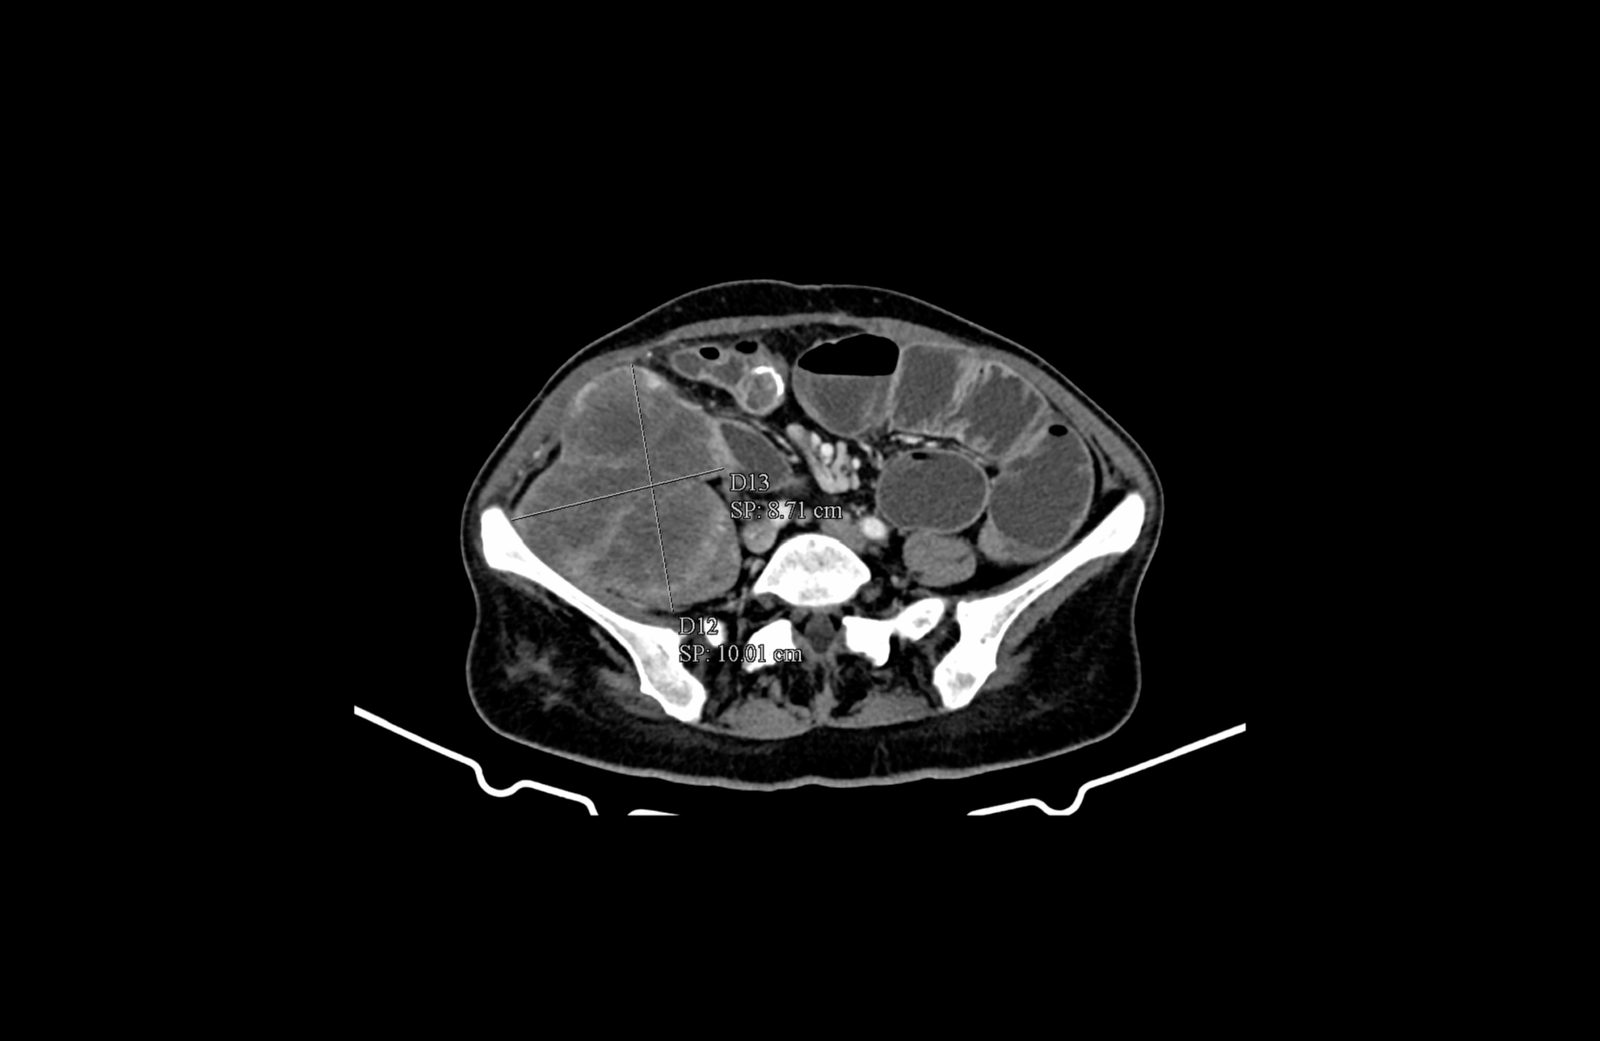

- инфилтрация на m. iliacus, граничеща с илиачната кост

Медиална компресия и деформиране на лумените на десните общи и външни илиачни съдове. Прорастване на тумора през цялата дебелина на m. iliacus

Инфилтрация на меките тъкани на предната коремна стена

Инфилтрация на меките тъкани на предната коремна стена и m. iliopsoas, както и прилежащия към него n. femoralis